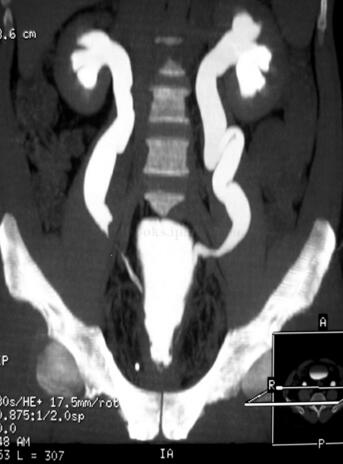

盆腔CT:盆腔内脂肪密度影增多,膀胱抬高前推(图46-2)。

图46-2 盆腔CT

图46-7 CT扫描:患者腹部膨隆(肥胖),膀胱位置抬高,双侧输尿管扩张、积水明显